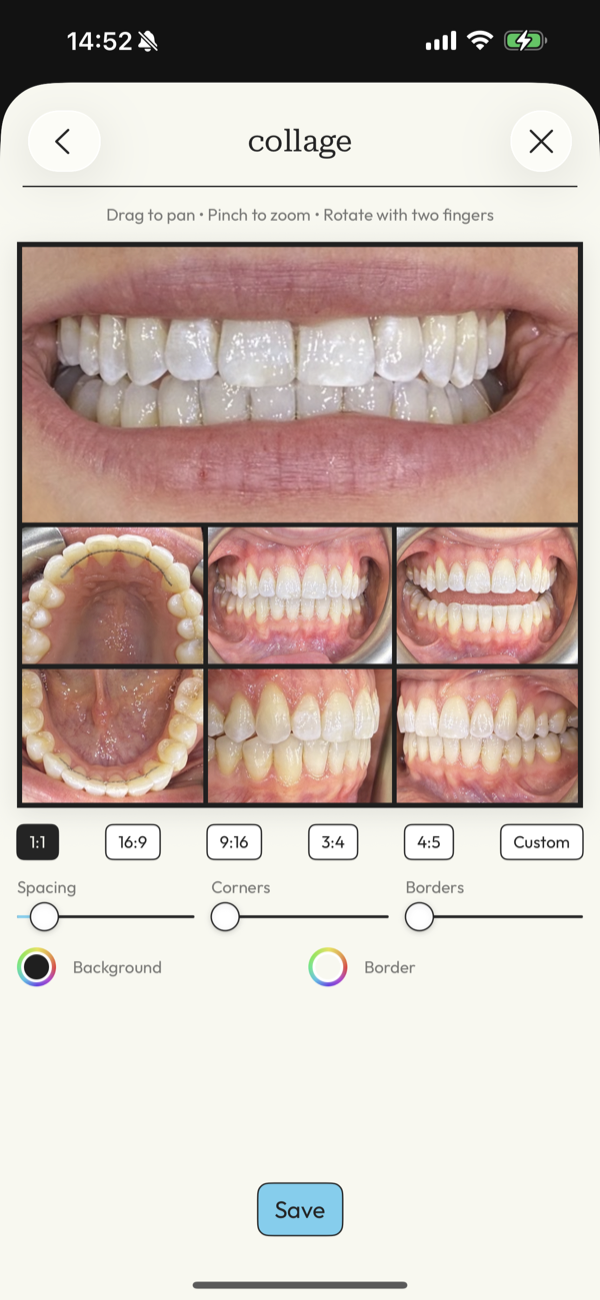

picture perfect images

Capture images with guided precision or import your DSLR work, then transform them into flawless before-and-after cases ready to present and share.